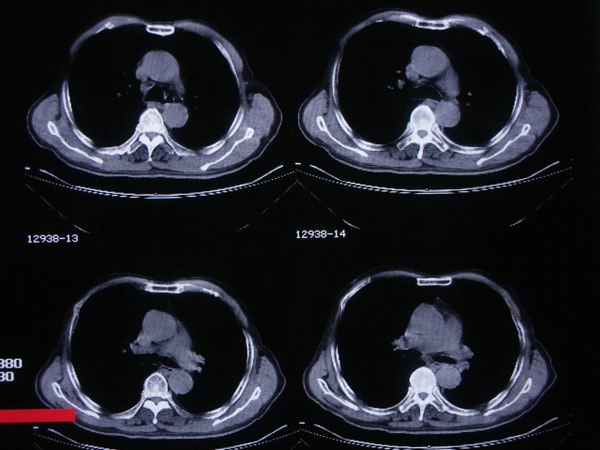

1.病史明确,考虑膀胱癌双肺以及肋骨转移。

2.前列腺轻度增大,形态欠规则,密度不均匀。右侧精囊明显肿大,双侧闭孔内肌肿胀、模糊。前列腺、精囊、闭孔内肌均考虑有转移病灶。